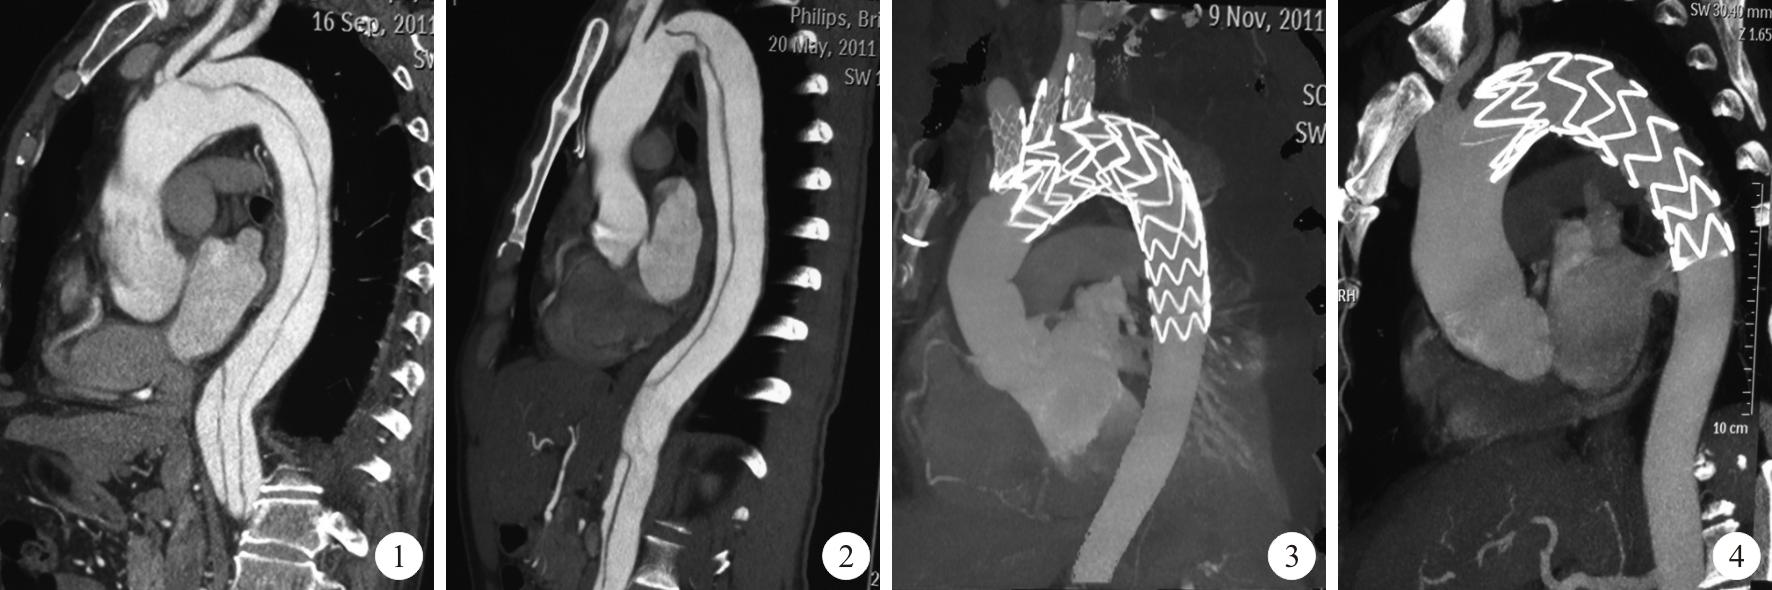

外科开放手术主动脉夹层患者开放手术治疗目前主要用于standford A 型病人,但截瘫发生率可高达5%~40%,其死亡率与内科药物治疗无明显差异。随着人工血管的不断发展,国内孙立忠等首次使用支架“象鼻”术治疗Stanford A 型主动脉夹层,此手术方式的优点是覆盖了夹层内膜破口,扩大真腔,缩小假腔,增加血供。 腔内修复治疗1998 年,Dake 等首先采用腔内修复治疗Standford B 型夹层,此后得到不断发展及改进,从近十年的治疗结果来看,腔内治疗Standford B 型主动脉夹层安全有效,创伤小。

腔内修复治疗的时机选择夹层急性期由于主动脉壁会发生水肿,内膜脆弱,腔内修复术后会增加夹层内膜撕裂及主动脉破裂的发生率,但早期腔内修复有利于夹层真假腔的重构,因此Kato 等[10]提出应宜在发病4w 后、慢性期之前行腔内修复治疗,急性期应在发病3w 后给予腔内修复治疗,但对于有胸腔积液、疼痛无法缓解、主动脉分支血管缺血无法缓解及降主动脉直径>4.5cm者应急诊行腔内修复治疗, 以免在等待过程中发生夹层破裂及其他致命性并发症。

扩展锚定区由于腔内修复术要求近端锚定区应>1.0~1.5mm,对于部分主动脉夹层患者需扩展锚定区,国内外学者为此做了大量研究工作。延长锚定区的治疗进展主要有以下几个方面: Hybrid 技术根据夹层破口发生的位置分别采取不同的杂交技术来延长锚定区。若需覆盖左锁骨下动脉,常见方式为左颈总动脉 ̄左锁骨下动脉旁路;如需覆盖左颈总动脉,常用旁路方式有右颈总动脉 ̄左颈总动脉和右颈总动脉-左颈总动脉 ̄左锁骨下动脉旁路等; 若需覆盖无名动脉此时采用Debranch 技术,此方法需要切开胸骨,但无需体外循环,应用“部分阻断”技术,采用分叉型人工血管,将其近端与升主动脉侧壁吻合, 远端分叉与无名动脉和左颈总动脉吻合,根据术前情况重建或不重建左锁骨下动脉。如果病人不能耐受开胸手术可经左髂动脉到左腋动脉及左颈总动脉、右髂到右腋动脉血管旁路术来延长锚定区。但其远期通畅率不如Debranch 技术。

分支型及开窗型人工血管的应用开窗型人工血管是术前根据具体情况剪出或在人工血管膜上预留侧孔,覆膜支架近端超过分支血管开口,但可以经支架侧孔保证该分支血管的血流。另一种方法是在移植物中间开窗,但术中定位比较困难。分支型人工血管指在覆膜支架上带有侧支来保证血管分支的血流,常见的人工血管是带有一个分支和三个分支,带有一个分支的支架型人工血管能保留主动脉弓上一个分支动脉的血流,通常用于保留LSA。带有三分支人工血管能保留主动脉弓上三个分支动脉的血流。